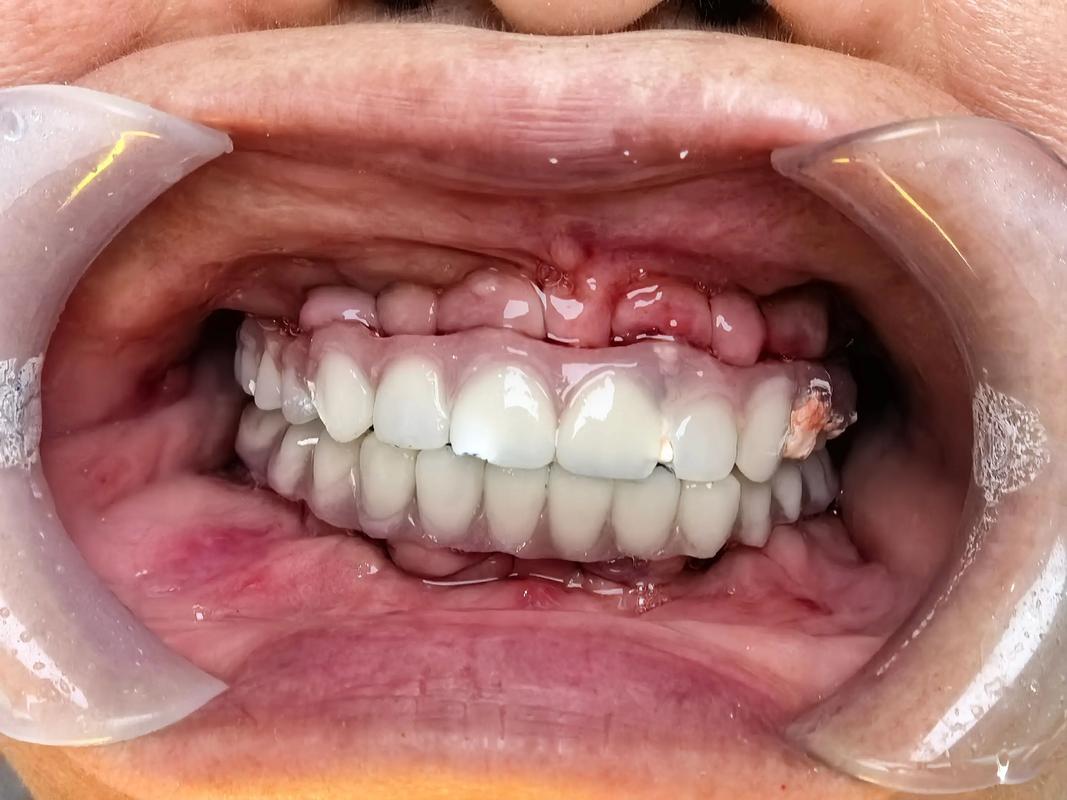

- 关键点: 这种临时牙冠必须非常轻巧,并且严格限制咬合力(只能吃软食),目的是在保证种植体稳定的前提下,尽快恢复美观和部分功能,同时维持牙龈形态。这需要医生有丰富的经验并严格筛选患者。

- 愈合基台: 在大多数常规种植中,种植体植入后会在上面安装一个“愈合基台”,它高出牙龈,引导牙龈形成漂亮的袖口形态,为最终戴牙做准备,这个愈合基台本身不是用于咀嚼的临时牙冠。

- 这个临时修复体是基于最终牙冠的模型制作的,形态、颜色和咬合都尽可能接近最终效果。

- 维持牙龈形态,防止牙龈萎缩。

- 恢复美观和基本功能(但仍需避免咬硬物)。

- 让患者提前适应最终牙冠的感觉。

- 保护种植体内部结构(基台)。

- 这个临时牙冠通常比骨结合期的临时修复体(如果有)更坚固一些,但仍需小心使用。